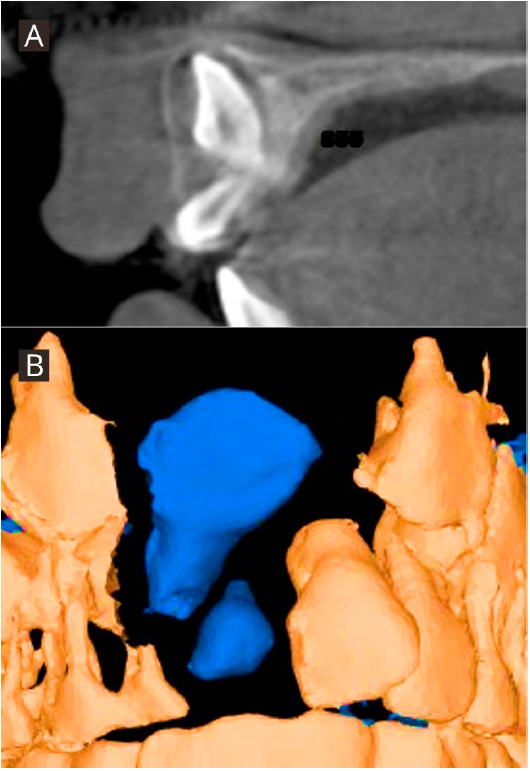

Paciente de género masculino de 8 años de edad, sin antecedentes mórbidos. Perfil convexo, clase II esqueletal. En el análisis intraoral se observó dentición mixta primera fase, diente parcialmente erupcionado en zona de diente 11, diente 21 mesiorotado, distoclusión molar bilateral, discrepancia óseo-dentoalveolar severa superior y moderada inferior, relación transversal desfavorable, líneas medias dentarias centradas (Figura 4. A-D). En el análisis con CBCT, realizado con el software Nemotec ® se observó el diente 11 en evolución intraósea en una posición alta, perpendicular al plano oclusal con formación radicular incompleta, ubicado hacia vestibular, con una distancia de 19.57 milímetros al borde incisal del incisivo central contralateral, y la presencia de un diente supernumerario parcialmente erupcionado, de forma coronaria cónica en zona del diente 11 (Figura 5. A-B).

Figura 5 Imágenes tomográficas. A. Corte sagital inicial de diente 11 evaluado en CBCT. B. Representación tridimensional de posición inicial de diente 11 evaluado en CBCT, vista frontal.

Los resultados obtenidos son favorables para ambos casos descritos. Respecto al caso número uno, en el control tomográfico el diente 21 presenta un soporte periodontal favorable, paralelismo radicular y proporción corono radicular 1:1 (Figura 7. A-B). Respecto al caso número dos, en el control tomográfico, el diente 11 presenta una posición adecuada en la arcada, una longitud radicular disminuida y un soporte periodontal con pronóstico reservado (Figura 8. A-B). Ambos casos clínicamente presentan un posicionamiento adecuado en el arco y no presentaron defectos mucogingivales posterior a la tracción.